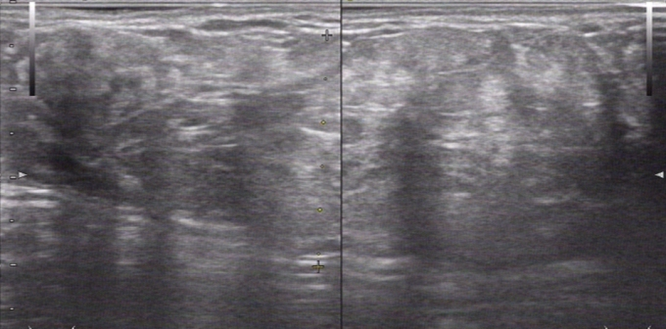

病例:女性 51岁 因右上臂肿物就诊

超声描述:右上臂肿物处探查:皮下软组织内见不均匀中强回声,边界清,大小约8.0*3.5cm,CDI:内见少量血流信号。

超声提示:右上臂皮下实性包块--考虑脂肪瘤

病理回报:送检物来异位的乳腺组织,呈纤维囊性乳腺病改变

附图